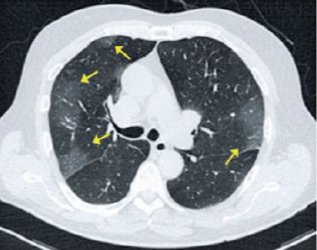

Paciente de 72 anos apresenta anosmia, febre e tosse há 3 dias. A principal hipótese diagnóstica é Covid-19. Quais achados na imagem tomográfica a seguir corroboram para esse diagnóstico?

Provas